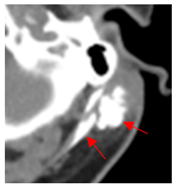

| 1 | 75–100 | 860 | ![]() Axial post-contrast fat-suppressed T1-weighted MRI shows a solidly enhancing left retroarticular tumor. | ![]() Axial CT image obtained 1 day after injection shows the NBTXR3 nanoparticles (arrows) in the tumor with leakage into the surrounding soft tissues. |